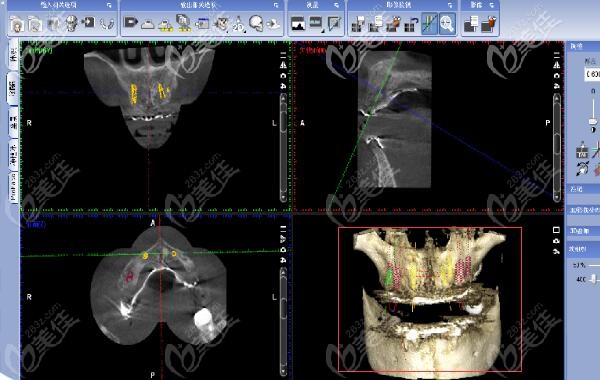

X线片和CBCT显示牙槽骨骨量充足。

治疗方案:全口种植;

上颌:埋入式植入6颗种植体,恢复3个月 ;恢复上颌14颗冠;

下颌:即刻拔出33、34、35 ;即刻种植6颗种植体即刻负重,恢复14颗冠 。共恢复牙冠28颗。

▼手术中▼